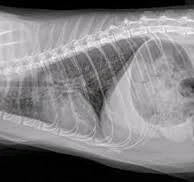

Chest Radiographs (X‑rays)

X‑rays are one of the most important tools for diagnosing asthma. They may show:

• Over‑inflated lungs (air trapping)

• A flattened diaphragm

• Thickened airway walls (often described as “doughnuts” and “tramlines”)

However, up to one‑quarter of asthmatic cats may have normal X‑rays, especially early in the disease.